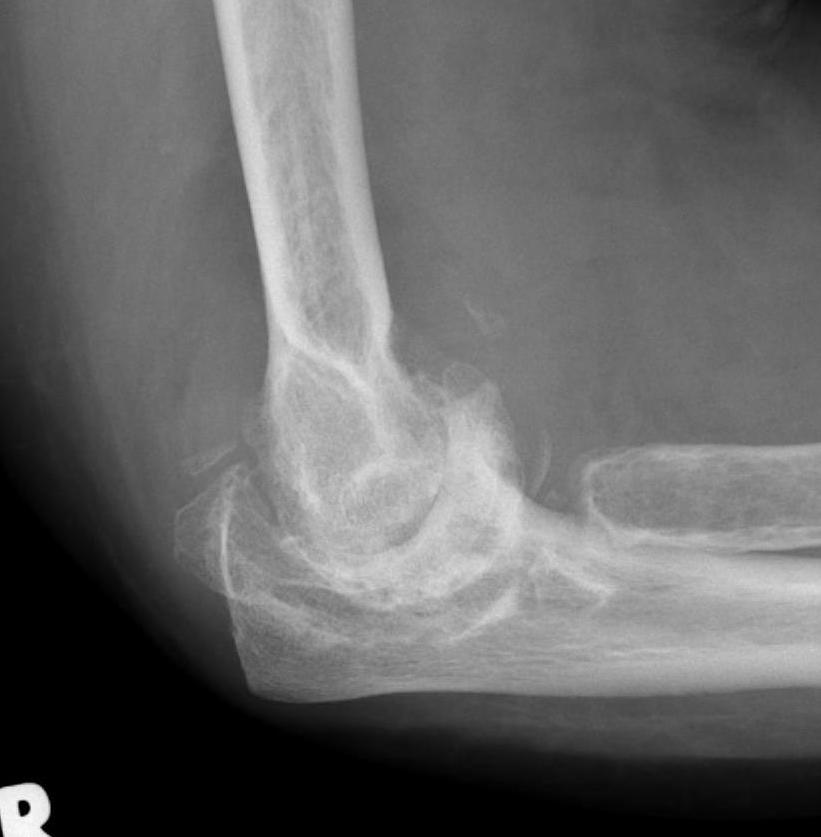

X-ray

Early stage

- preserved radiocapitellar and ulnohumeral joints

- osteophytes of the olecranon and coronoid

Lateral xray demonstrating olecranon and coranoid osteophytes